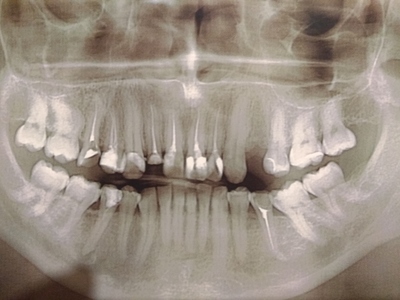

Сломался зуб, почти под самую десну.

На мои слова о том, что может сразу имплант ? Закатывают глаза "ну если вы так хотите, то можна и так" Но я же блин пришел к спецам. Если зуб был дважды пломбирован и сломался, то корни уже не лучшие.

В общем. Подскажите люди добрые. Если вы в теме. Прав я, в том, что не надо растягивать удовольствие на много серий. И сразу уже поставить имплант?